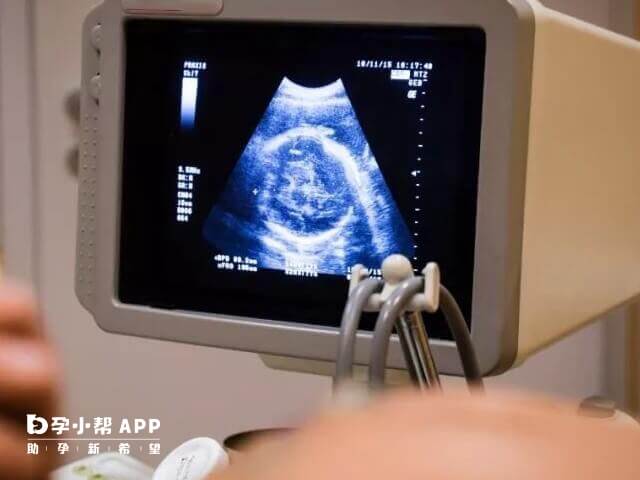

可以了解是否宫内妊娠,胚胎大小等情况,一般情况下,妊娠5周后可以看见孕囊,妊娠6周时妊娠囊检出率高,发现宫外孕要及时治疗,防止破裂大出血,危及生命。

了解子宫大小,是否与停经月份符合,胚胎是否发育正常,当子宫大小与停经月份不相合时,需B超检查,排除子宫肌瘤、子宫发育异常、胚胎发育异常。